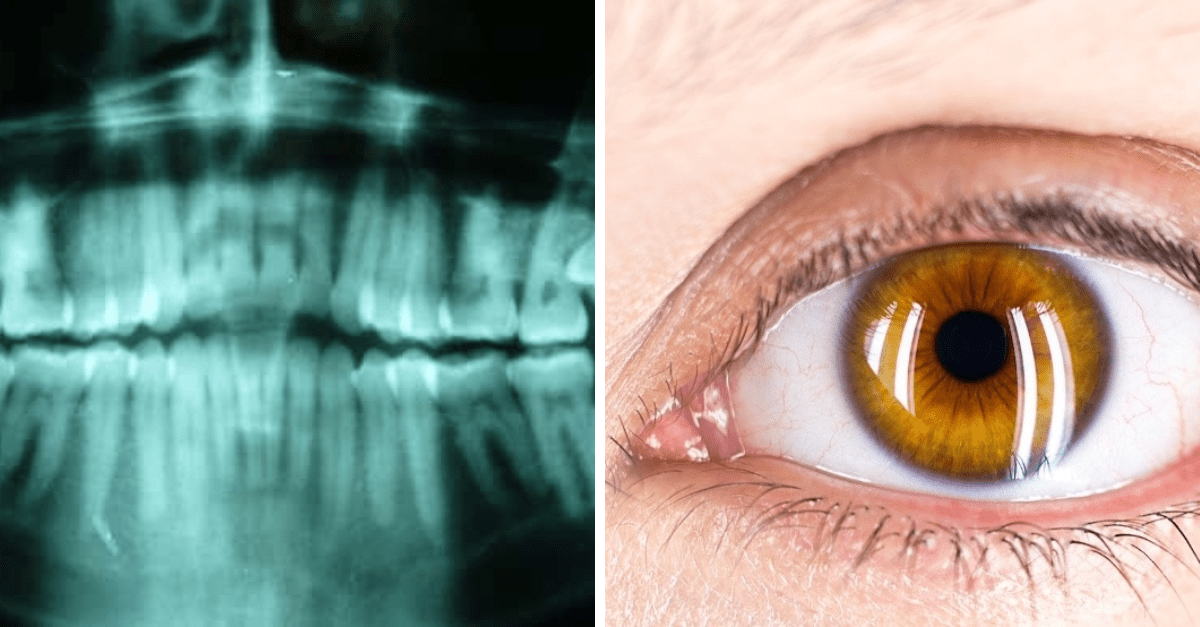

Plica semilunaris

Všimli ste si nenápadnú ružovú riasu vo vnútornom kútiku vášho oka? Ide o pozostatok tzv.tretieho viečka, nazývaného aj plica semilunaris, ktorá slúžila napríklad na zvlhčenie oka alebo ako ochrana pred nežiadúcimi čiastočkami.

V súčasnosti pozostatok pomáha pri pohyboch oka a odvádzaní sĺz do slzného kanála.